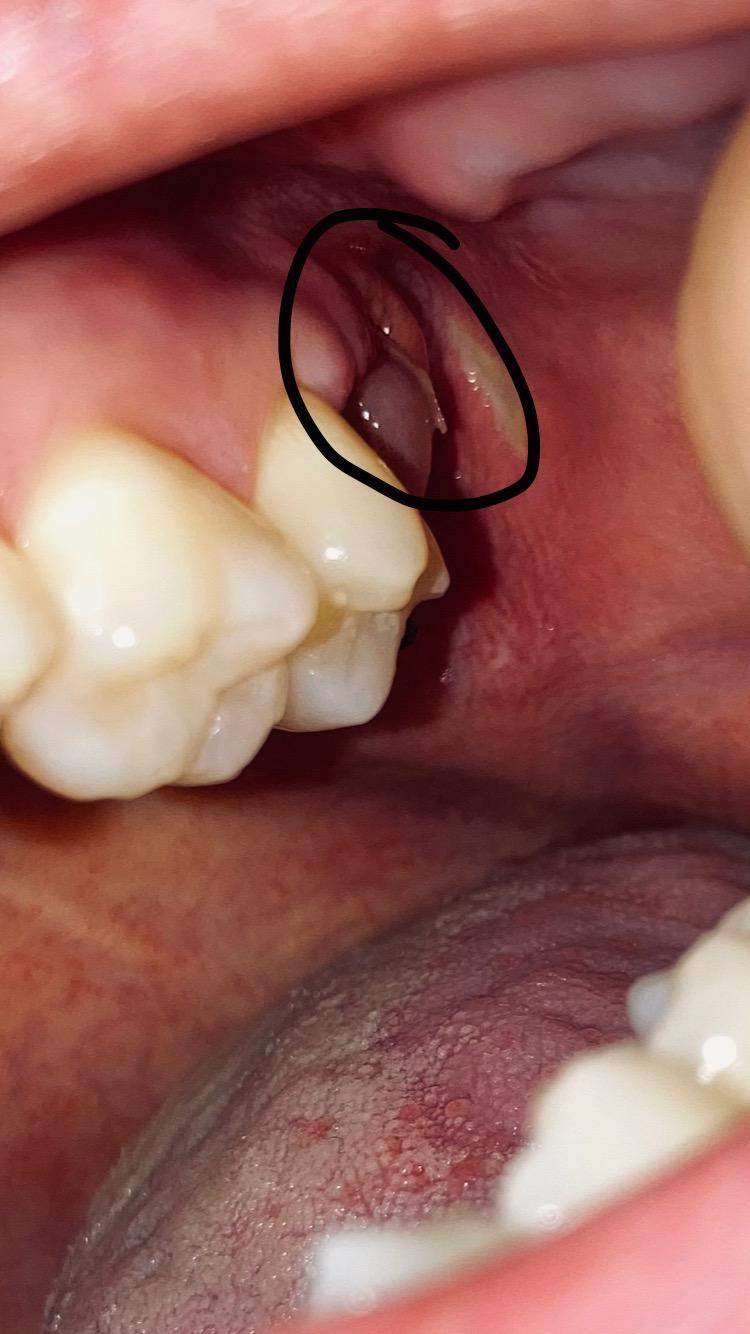

Dies ist zwar normal, kann aber unangenehm oder schmerzhaft sein. Entdecken Sie, was zu tun ist, wenn nach einer Zahnextraktion der Knochen aus dem Zahnfleisch kommt und wie Ihr Zahnarzt helfen kann.

Zahnentfernung Zahnextraktion Zahn muss raus Schritt für Schritt Anleitung, praktische. Des Weiteren schwillt der Bereich, in dem der Zahn extrahiert wurde, während der Heilung oft an Wie kommt es nach einer Zahnentfernung zum Zahnfleischrückgang? Wenn ein Zahn gezogen wird, dann kommt es im Anschluss oftmals dazu, dass sich das Zahnfleisch kurzfristig zurückbildet und auch das Zahnfleisch der umliegenden Zähne kann davon betroffen sein

Zahnentfernung Zahnextraktion Zahn muss raus Schritt für Schritt Anleitung, praktische. Entdecken Sie, was zu tun ist, wenn nach einer Zahnextraktion der Knochen aus dem Zahnfleisch kommt und wie Ihr Zahnarzt helfen kann. Wieso entstehen Schmerzen nach dem Ziehen eines Zahns? Einerseits werden das Zahnfleisch und der umliegende Knochen während des Extraktionsprozesses irritiert